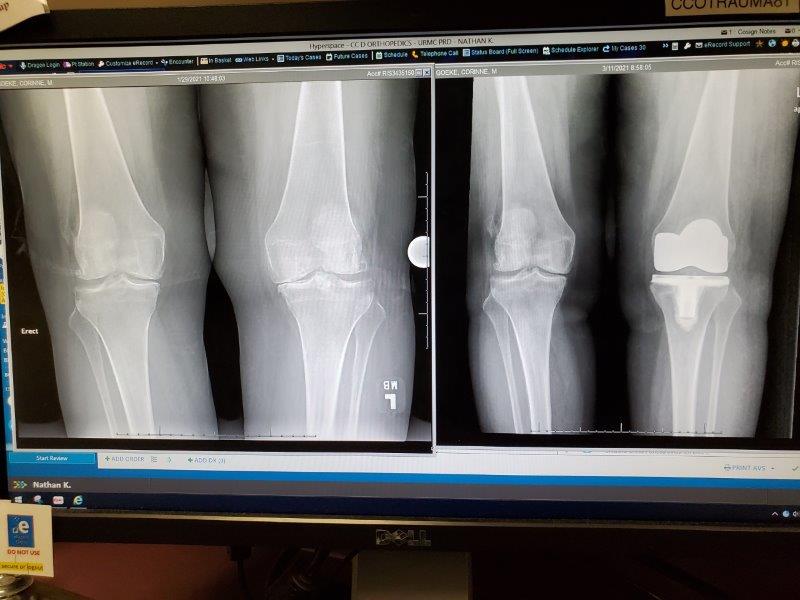

I saw a knee orthopedic doctor as soon as I could and received the startling news that I needed a full knee replacement. What???? In the past I had been told I had arthritis in my knees, but no one ever said the words “knee replacement.” It was a total shock. I received a cortisone shot and the replacement was scheduled for February 8 with an excellent surgeon.

February 8th rolled around and my surgery happened. My surgeon did a great job.

I joined up with them a week later. I was 9 weeks post surgery and things were going well. Give it a year and I’ll be as agile as Jim and his two knee replacements.

Yes, the new knee is doing well. When the next knee goes (and it will), I won’t hesitate to get that one done too. ๐